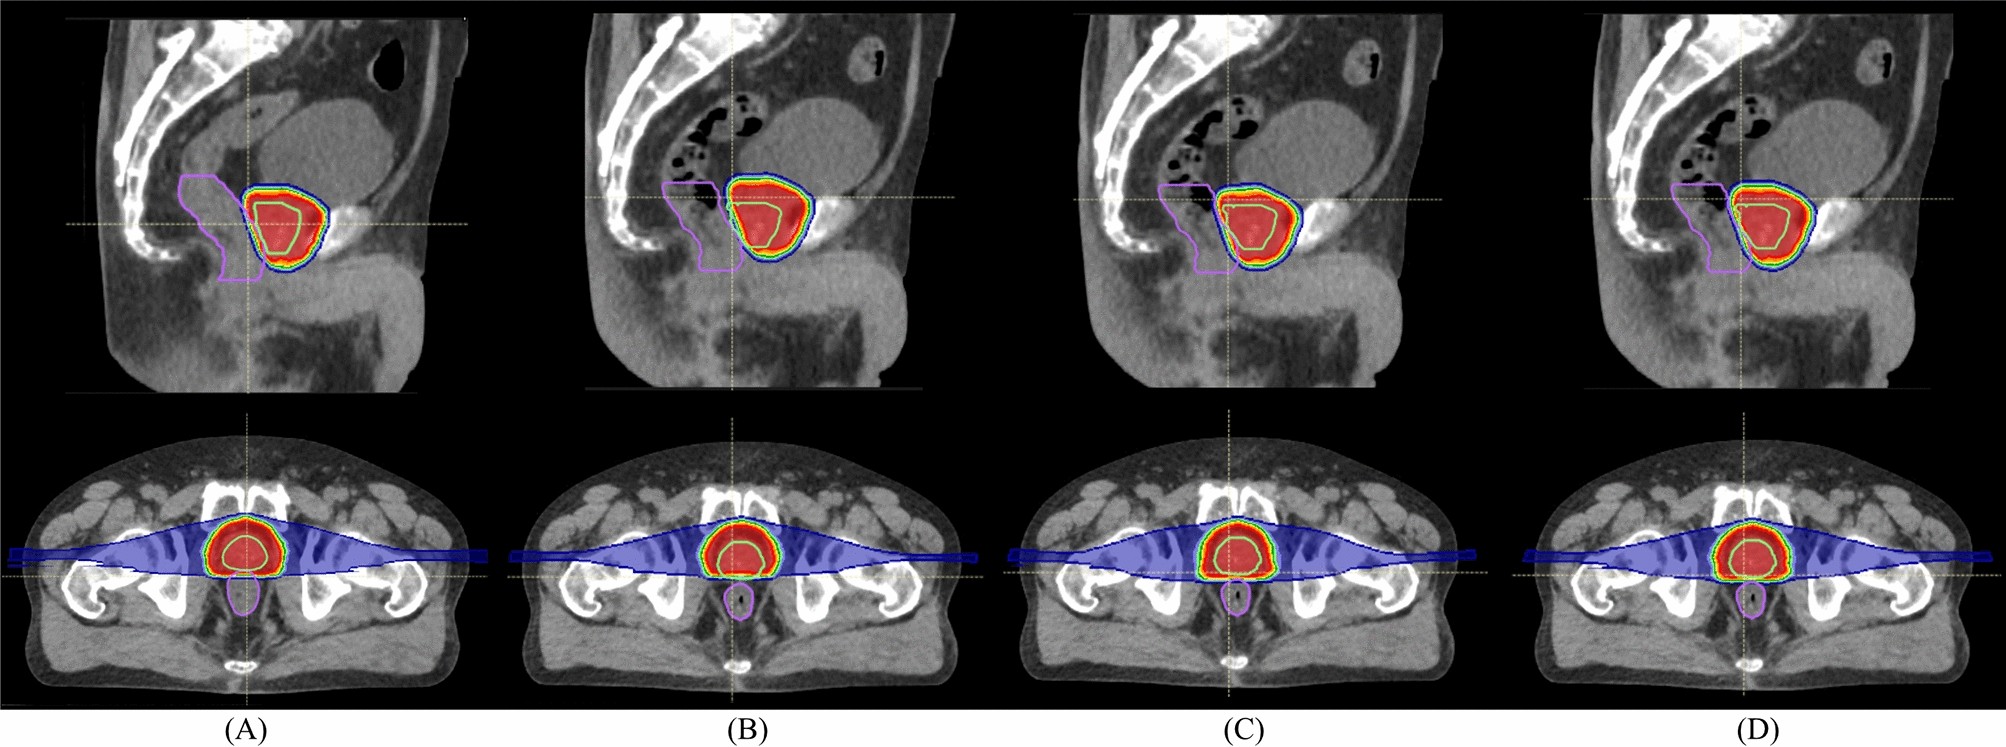

Figure 3

Dose distributions (case no.7) on (A) the planning CT and on the treatment CT (CT1) with (B) intensity-based image registration, (C) target-based image registration, and (D) WEPL-based image registration. Light green and purple lines outline the CTV and rectum, respectively.